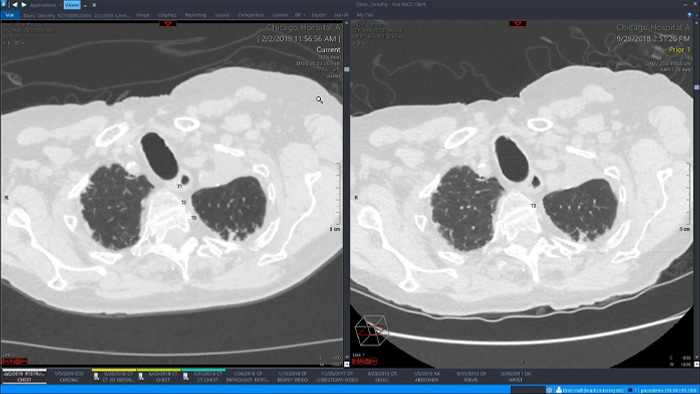

Analicemos algunos de los beneficios inmediatos de un enfoque unificado. Un espacio de trabajo único y unificado para radiología incorporaría funciones avanzadas de posprocesamiento 3D y distribución de imágenes, que se abrirían en un visor adicional para facilitar el trabajo.

Mediante un espacio de trabajo unificado, los usuarios podrían iniciar fácilmente las herramientas de análisis pertinentes desde las más de 70 aplicaciones avanzadas disponibles en varios dominios clínicos. La inteligencia artificial puede desempeñar un importante papel a la hora de automatizar las tareas y flujos de trabajo y predecir los patrones de uso.

Un espacio de trabajo unificado y completamente integrado en la plataforma de adquisición de imágenes empresarial y en el visor de diagnóstico, ofrece un acceso sencillo y eficaz a todas las herramientas necesarias en todos los ámbitos clínicos. El acceso con un solo clic a herramientas de visualización avanzadas, como la colonoscopia virtual, el procesamiento 3D y la adquisición de imágenes espectrales, permite una interpretación eficaz y aumenta la fiabilidad del diagnóstico.

Proporciona un espacio de trabajo único con herramientas relevantes para leer con confianza y elaborar informes perspicaces, mejorando el flujo de trabajo y la productividad mediante el uso de funciones 3D nativas integradas e informes multimedia.

Ofrece funciones de visualización avanzada con un sólido conjunto de herramientas para la evaluación cuantitativa asistida por IA y la generación automática de resultados.